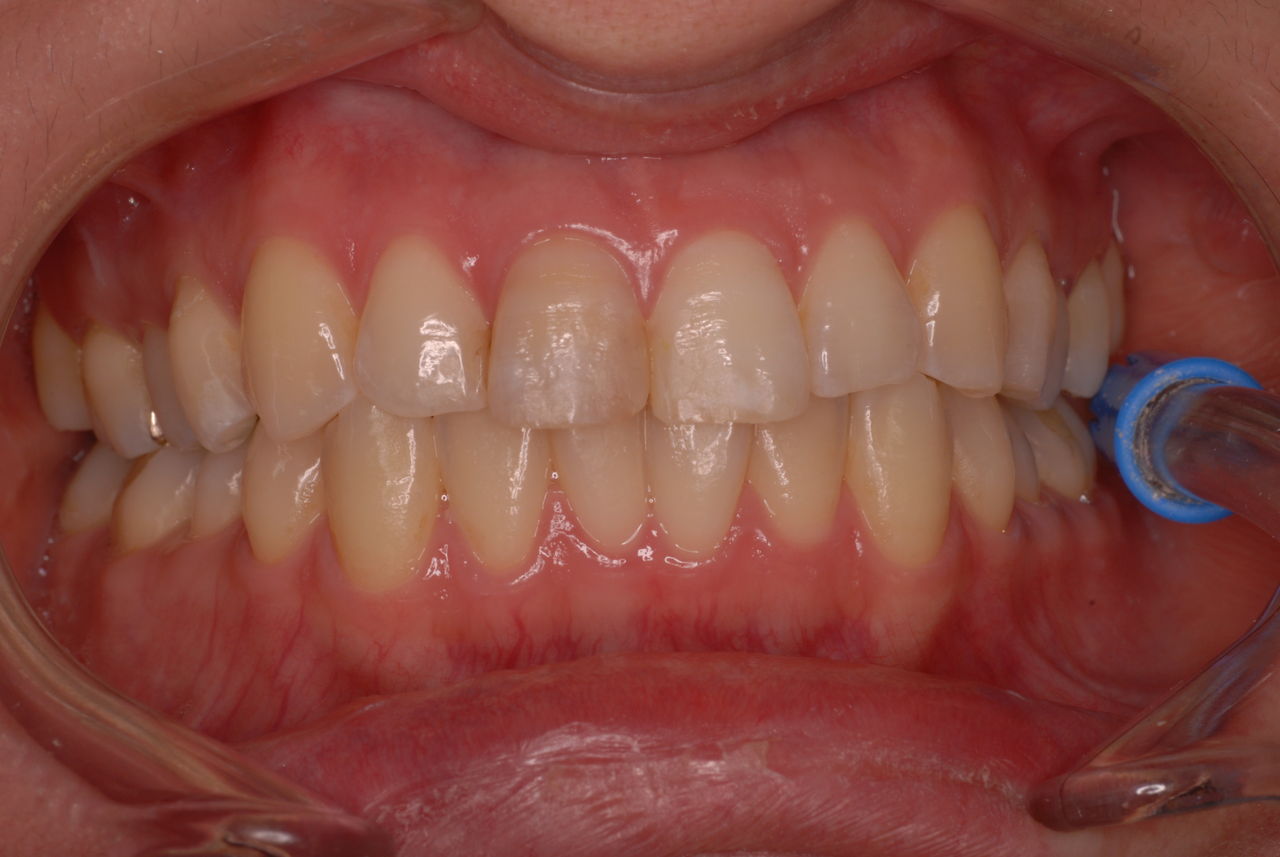

色々不満な入れ歯です。

発音や見える金属が気になるようです。